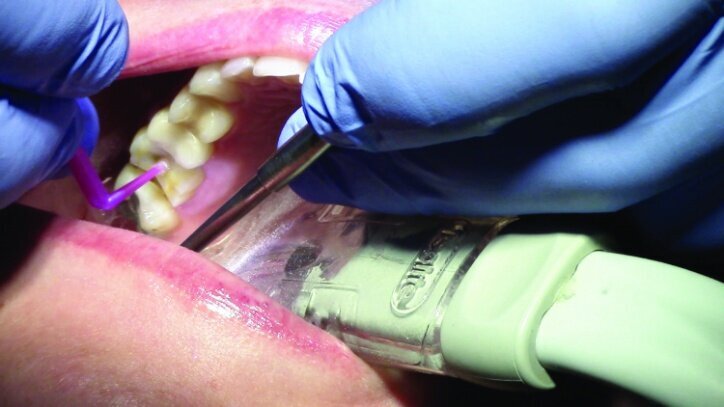

The teeth were isolated using Isolite (Fig. 27). Multilink Primer A/B was scrubbed onto the entire bonding surfaces using a microbrush for 30 seconds. Excess material was dispersed with blown air until the mobile liquid film was no longer visible, leaving a glossy appearing surface (Figs. 28 & 29).

An OptraStick Application Aid (Ivoclar Vivadent) was used to seat the restorations on the teeth because onlays and partial crowns can be difficult to handle. Initial tack curing was completed using a Bluephase curing light (Ivoclar Vivadent) for three seconds at each interproximal area. The resin was then removed easily using a 36/37 scaler from Brasseler. Liquid Strip (Ivoclar Vivadent), a glycerine gel that prevents an oxygen-inhibited layer of the resin cement, was applied to the margins prior to final curing (Figs. 30 & 31).